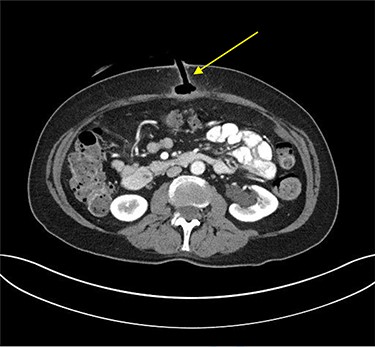

Erect plain chest radiograph was normal. Computed tomography (CT) imaging of the abdomen and pelvis demonstrated evidence of PEG tube dislodgement with the internal bumper positioned in the subcutaneous tissue and the distal tip of the tube in the tract beyond the stomach wall, consistent with a diagnosis of BBS (Fig. 2).

Transverse plane of CT of abdomen and pelvis illustrating the migration of the internal bumper of the PEG and the sealing of gastric mucosa as indicated by the yellow arrow.